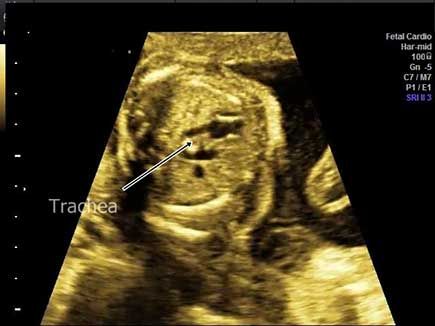

Challenge your anatomy skills: Can you identify the spinal structure?